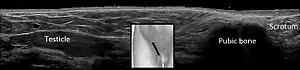

In the minority of cases with bilaterally nonpalpable testes, further testing to locate the testes, assess their function, and exclude additional problems is often useful. Scrotal ultrasound or magnetic resonance imaging performed and interpreted by a radiologist can often locate the testes while confirming absence of a uterus. At ultrasound, the undescended testis usually appears small, less echogenic than the contralateral normal testis and usually located in the inguinal region. With color Doppler ultrasonography, the vascularity of the undescended testis is poor.